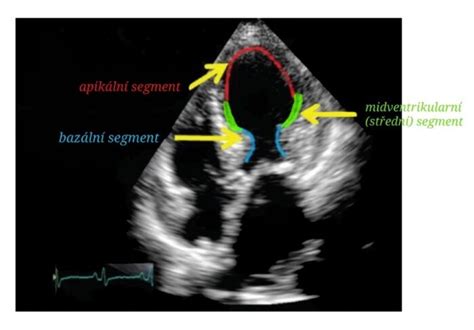

- Srdce: Dôkladne sa vyšetrujú srdcové komory, predsiene, chlopne a cievy. Sleduje sa veľkosť 4 komôr, či sú prepojené chlopňami a tie sa správne pri každom údere srdca otvárajú a zatvárajú.